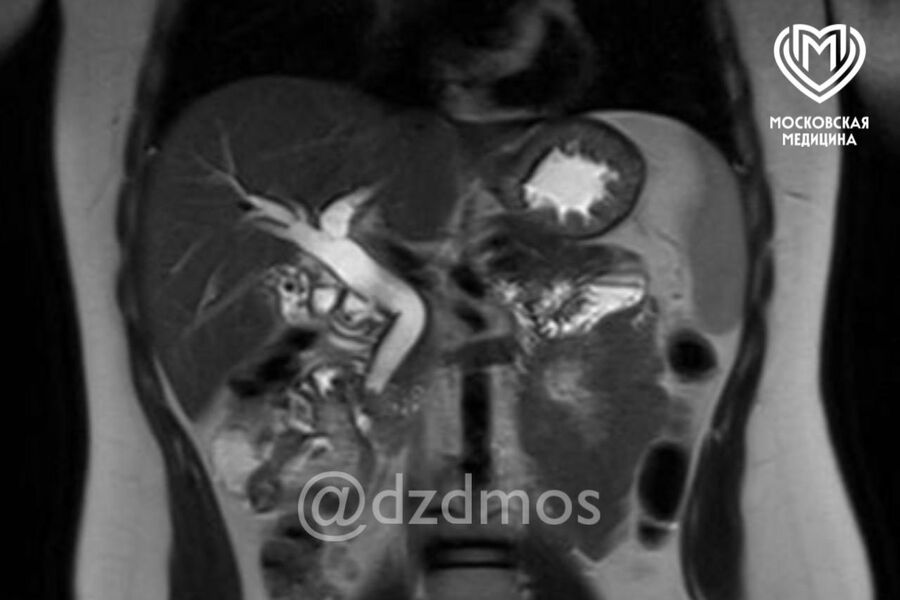

Ребенок поступил в медицинское учреждение с болями в животе, рвотой и общей слабостью. Обследование показало, что в желчном пузыре ребенка скопилось огромное количество камней диаметром до 3 мм. Один из них перекрыл общий желчный проток, что угрожало жизни девочки.

«Ребенку сделали эндоскопическую папиллосфинктеротомию: специальным аппаратом рассекли сосочек, впадающий в желчный проток, расширили его мышечное кольцо и извлекли камень. Вторым этапом удалили желчный пузырь, полностью забитый камнями», — рассказали в пресс-службе депздрава.